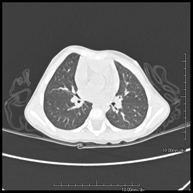

- Chest CT

Diagnostic test that provides high definition anatomical images of the chest (lungs, heart, mediastinum, great vessels, rib cage, etc.) using CT (Computed Tomography) equipment. These images are then examined on a workstation that allows bidimensional reconstructions in different planes of space and also 3D reconstructions (volumetric). Some studies require the use of an iodinated contrast agent to improve image definition.